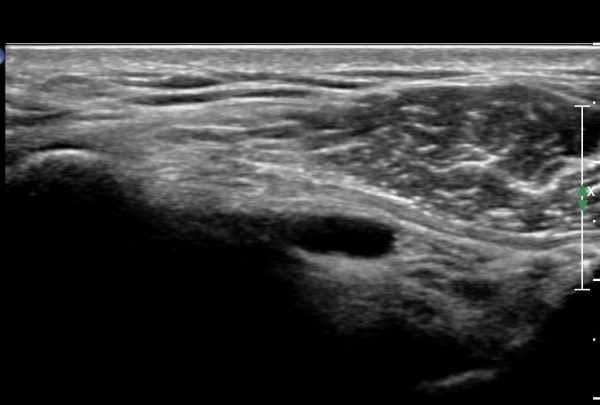

ȸÀü±Ù°³°£°Ý(rotator cuff interval)  Ⱦ´Ü¸é°Ë»ç¿¡¼­ ±¹»ó°Ç ³»ÃøÀÇ °Ç ¶Ñ²²°¡ ¾ã¾ÆÁø °ÍÀ¸·Î

º¸¿© ±Ø»ó°Ç ³»Ãø ºÎºÐÆÄ¿©¸ª ¾Ï½ÃÇÔ(»çÁø 3, ).